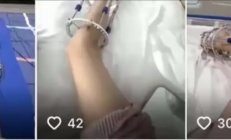

央视曝光断骨增高灰色产业链:女子出国做手术腿部严重感染喷脓